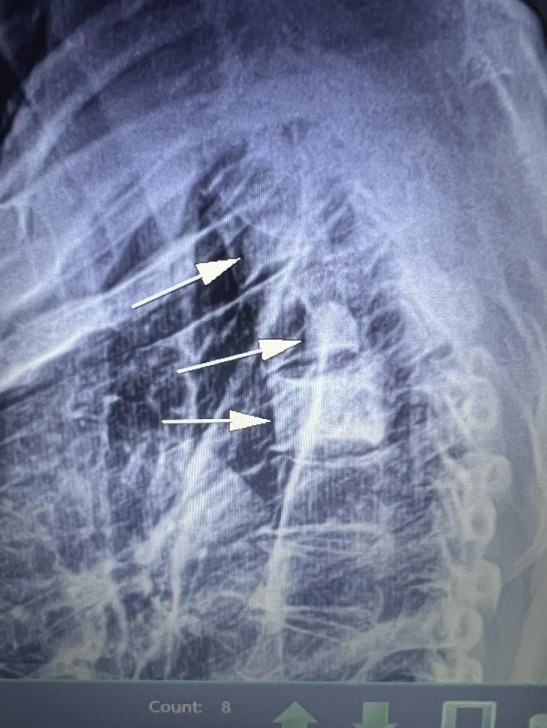

AFN.az xəbər verir ki, tanınmış həkim Aydın Əliyev bu sahədə vəziyyətin getdikcə ağırlaşdığını bildirib. O, xəstələrdən birinin müayinə nəticələrini paylaşaraq bunları yazıb: “Onkoloji xəstəliklərin müayinə və müalicəsinin hələ də icbari tibbi sığorta tərəfindən qarşılanmamasının daha bir qurbanı. Sağ qamış sümüyündəki törəmənin maddi imkansızlıq səbəbindən vaxtında və sistemli müalicə və ya əməliyyat edilməməsi səbəbindən fəqərələrə, qabırğalara, kürək, çanaq sümüklərinə, ağciyərə çoxsaylı metastazları. Demək olar ki, adam həyatını itirib”.